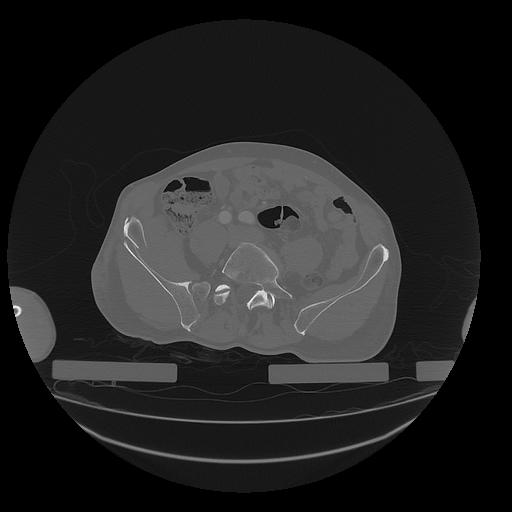

31 PULMON,CE,Vol,1.0,PULMON,,